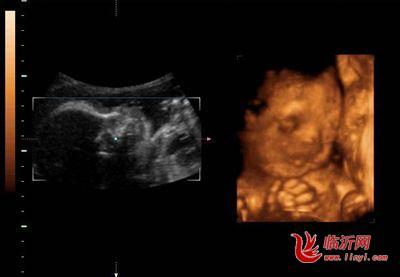

怀孕28周胎宝宝体重已有1100-1400克,坐高约为26厘米,几乎已经快占满整个子宫空间。此时胎宝宝正在做梦呢,是梦到妈妈你的模样?还是梦到好吃好喝的啦?呵呵,咱们谁也不知道。但是胎宝宝大脑活动在这时是非常活跃的,大脑皮层表面开始出现一些特有的沟回,脑组织快速增殖。祝福亲爱的小宝贝,做个好梦吧!

这个月的胎宝宝体重已有1100-1400克,坐高约为26厘米,几乎已经快占满整个子宫空间。

他的眼睛既能睁开也能闭上,而且已形成了自己的睡眠周期。有趣的是,他甚至会把自己的大拇指或其他手指放到嘴里去吸吮。这时的胎宝宝活动比较频繁,他会用小手、小脚在你的肚子里又踢又打,有时还会让自己翻个身,把你的肚子顶得一会儿这里鼓起来,一会儿那里又鼓起来。当然,也有的胎宝宝相对比较安静,动作相对少一些。胎宝宝的性格在此时已有所显现,奇妙吧!